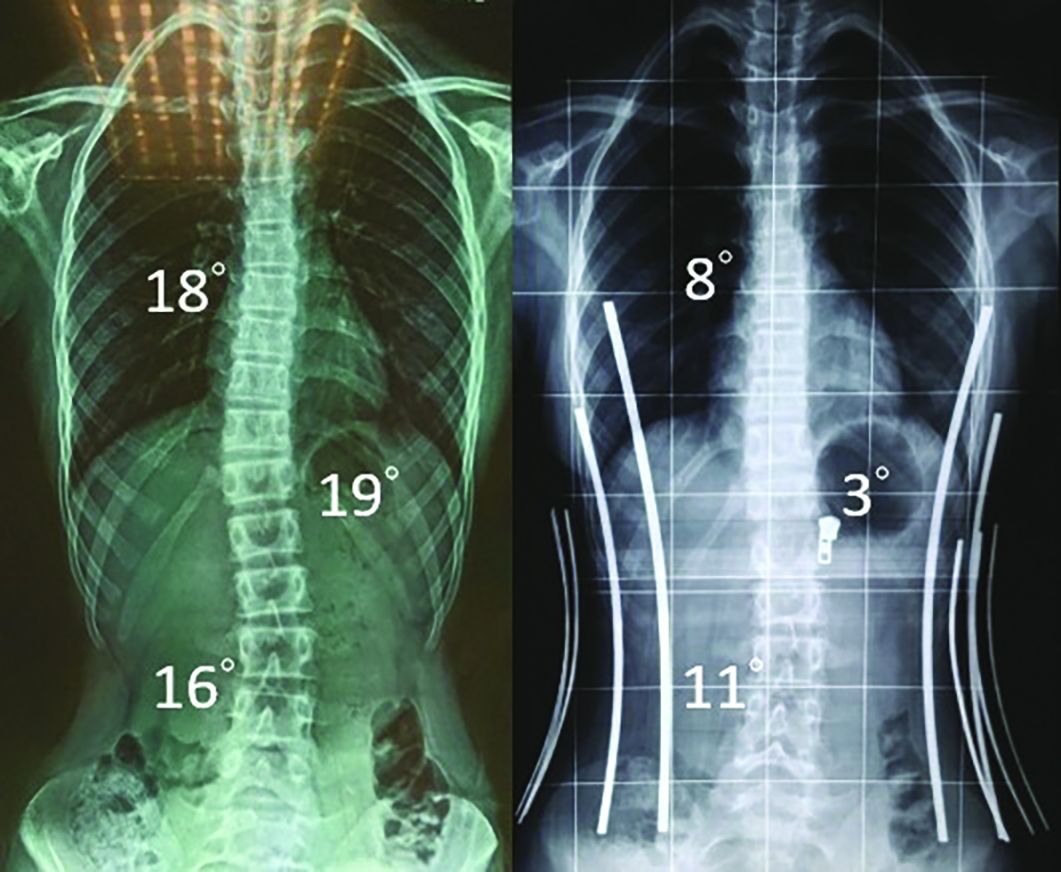

The innovative scoliotic brace is a functional garment specially designed for adolescents with scoliosis. The shape memory alloy (SMA) and the artificial hinges used in this design apply strategic corrective forces to the spine, providing adequate support to the wearers. Combining clinical practice, materials science and textile technology, the scoliotic brace of high wearing comfort can control the progression of spinal deformities more effectively and improve patient compliance, thus reducing the possible need for orthotic interventions or surgery.